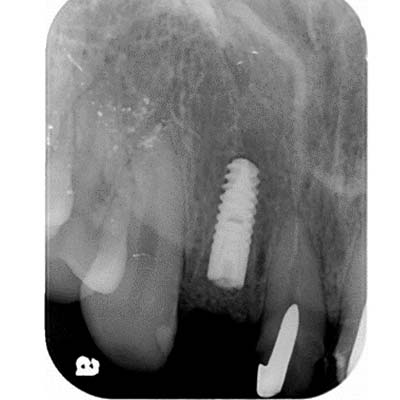

當日在拔除牙齒後,立即在拔牙窩洞裡,置入適當尺寸的植體,並在使用人工骨粉填塞縫隙。

根尖X光片

"4個月骨整合完成後,利用植牙支台齒,製作全瓷冠,恢復外觀"